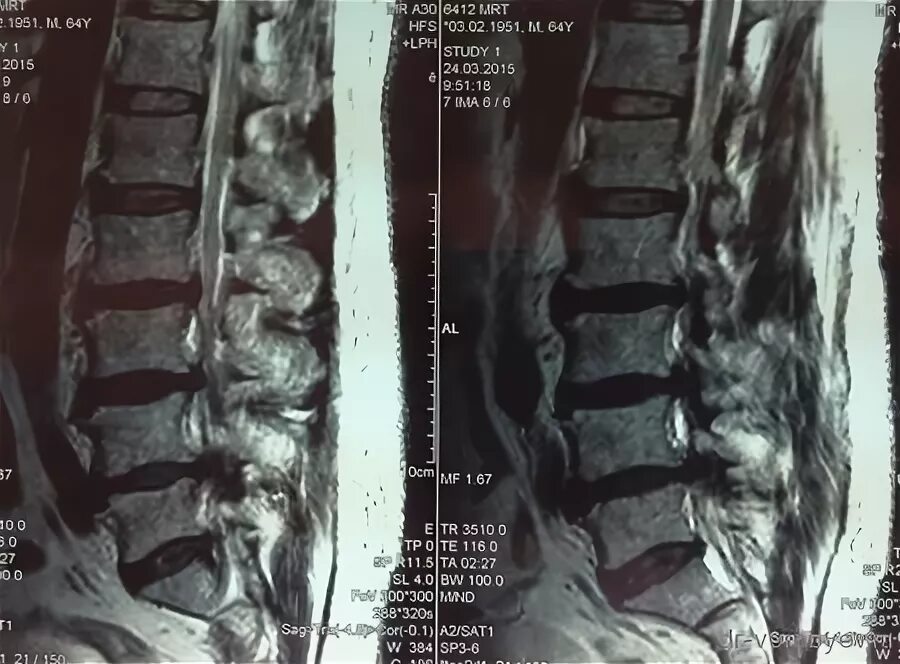

Можно ли делать мрт после операции